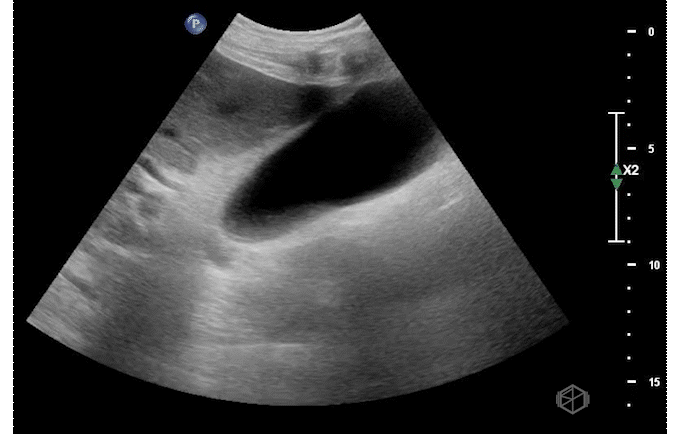

Ultrasound of the right upper quadrant demonstrated the below:

This ultrasound demonstrates a dilated common bile duct with mild gallbladder wall thickening.

• Finding the common bile duct is often difficult for novice sonographers. The common bile duct lies on top of the portal vein in long orientation making a “double barrel” type configuration as seen above. Color doppler may be used to determine the duct as there should be no flow. This is often easier to identify than the “Mickey Mouse” in short orientation.

• Due to the difficulty in determining the difference between the common hepatic duct and the common bile duct, some prefer to just call this structure the common duct (504652).

• If the labs are normal and there is no gallbladder wall thickening, pericholecystic fluid, or sonographic Murphy’s — there is little utility in finding the CBD (29162442).

• The CBD is measured inner to inner. There are various average sizes and no standard cut off but a common rule of thumb is that a dilated common bile duct is considered >4mm, increasing by 1 every decade at 50 and after. So a 70-year-old can have up to a 7mm sized CBD (14510259).

• Later studies have questioned this, however it is still considered a rule of thumb (28668951). In general, the CBD should remain under 6-7mm which is commonly accepted range for normal (11065260).